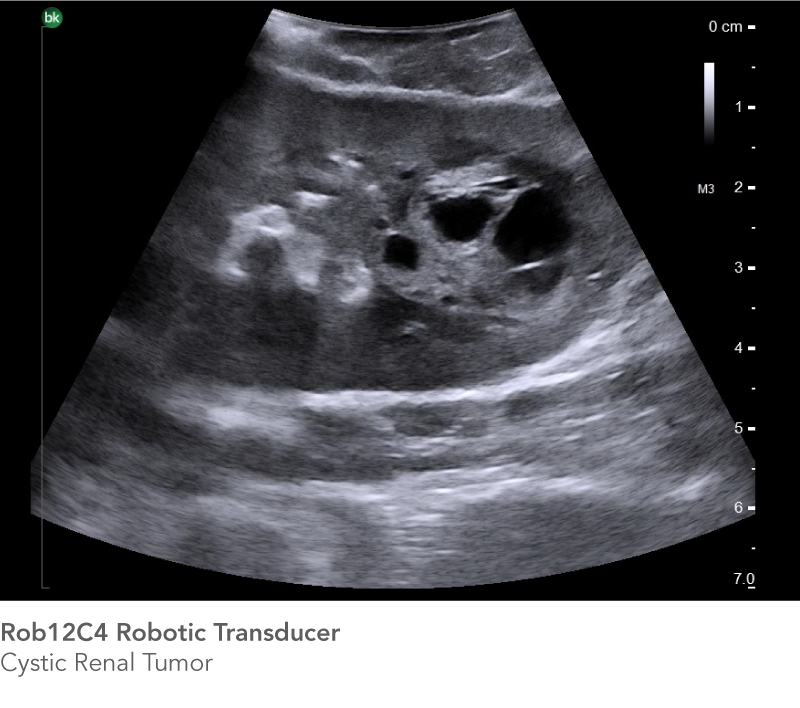

Partial Nephrectomy

See the information you need to achieve successful outcomes

Real-time intraoperative ultrasound helps you confirm tumor borders and depth, and minimize warm ischemia time, positive margins, damage to arteries, and resection of healthy tissue. The Rob12C4 transducer features a highly flexible cable and a small transducer profile, while the bk5000 offer's outstanding image quality with excellent anatomical details, enabling you to reach difficult-to-access anatomy and see the information you need to achieve successful outcomes.